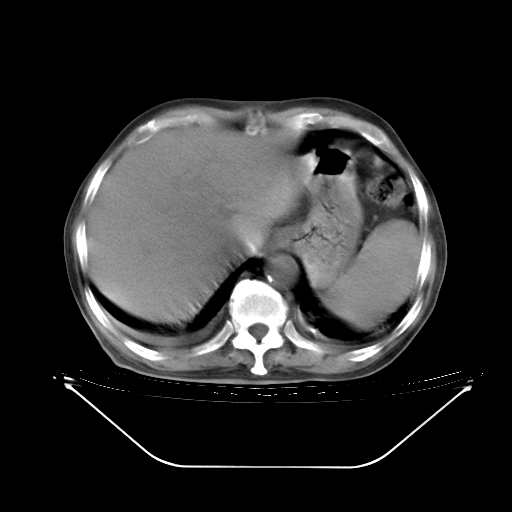

胸腹部CT,诊断意见:左上肺叶钙化灶、左侧胸膜局限性增厚并钙化、胆囊炎。描述部分肺组织呈磨玻璃样改变。